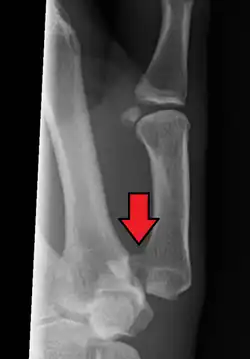

Bennett's fracture or Bennett fracture is a type of partial broken finger involving the base of the thumb, and extends into the carpometacarpal (CMC) joint.[1]

This intra-articular fracture is the most common type of fracture of the thumb, and is nearly always accompanied by some degree of subluxation or frank dislocation of the carpometacarpal joint.

Though these fractures commonly appear quite subtle or even inconsequential on radiographs, they can result in severe long-term dysfunction of the hand if left untreated. In his original description of this type of fracture in 1882, Bennett stressed the need for early diagnosis and treatment in order to prevent loss of function of the thumb CMC joint, which is critical to the overall function of the hand.[4]